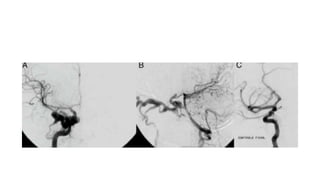

DSA

a.Digital angiogram of carotid circulation confirming carotid-cavernous

fistula

b. Digital angiogram of vertebral circulation showing right ophthalmic

vein ingurgitated.

C.Digital angiogram with final image after treatment of the traumatic

CCF

DSA a.Digital angiogram ofcarotid circulation confirming carotid-cavernous fistula b. Digital angiogram of vertebral circulation showing right ophthalmic vein ingurgitated. C.Digital angiogram with final image after treatment of the traumatic CCF